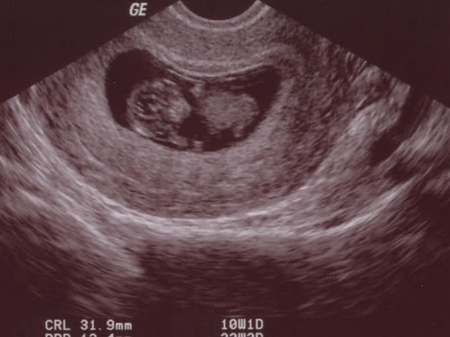

怀孕第6周胎儿长到0.85厘米,胎儿头部、脑泡、额面器官、呼吸、消化、神经等器官分化,通过B超可以清晰的看见胎囊,并能见到胎芽及胎心跳。所以,怀孕6周可以看到胎心胎芽。

胎心就是胎儿的心跳,胎儿在怀孕6周的时候,心脏像葵花籽仁一样大小,但已经会开始跳动了,每分钟可以跳动150次,相当于大人的两倍,当然此时只能用通过B超看到胎心搏动,还无法听到胎心胎动。

怀孕第6周,一般是可以通过B超看到胚芽了,此时胚芽大小在0.5-1厘米左右,形状像个小海马。但是别看他小,胎儿头部、脑泡、额面器官、呼吸、消化、神经等器官都已经开始发育了。当然也有些孕妇此时是看不到胚芽的。